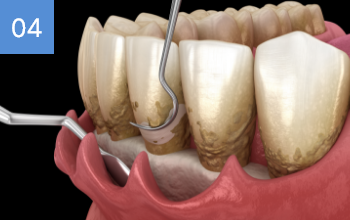

깊게 박혀잇는 고난이도 케이스, 잇몸절개 후 치아 분리하여

발치하였으며